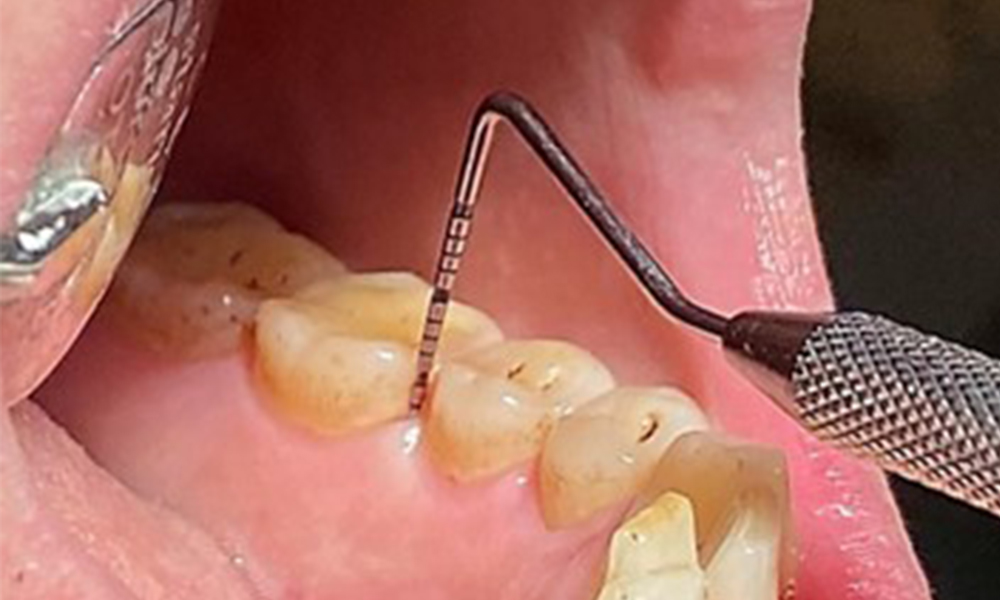

În contextul stării clinice generale favorabile, necesarul de măsuri individuale, ce urmează a fi determinat în cursul examinării intraorale, va avea un rol deosebit de important în planul de tratament. Va fi esențială determinarea periodică a profunzimilor de sondare. Sângerarea gingivală se diminuează la fumători, motiv pentru care diagnosticul clinic de parodontoză nu poate fi pus decât prin sondare (fig. 7). Punerea accentului exclusiv pe determinarea indicilor de sângerare poate masca prezența bolii parodontale și/sau a gingivitei existente. (5)

- Constatările obținute în timpul ședinței de tratament vor fi consemnate în fișa pacientului. Astfel, la fiecare vizită, se vor determina indicele de sângerare la sondare (BOP), în scopul evaluării adâncimii pungilor parodontale în stadiile incipiente ale bolii. Acest lucru este deosebit de important în cazul fumătorilor, datorită perfuziei tisulare reduse.